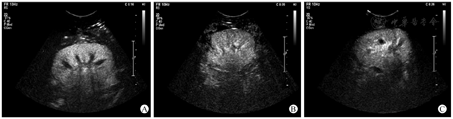

TRAS受者共23例,其中男性16例,女性7例,年龄为(42.62±13.7)岁。23例TRAS受者均行血管介入治疗,其中19例行单纯移植肾动脉球囊扩张术,4例行动脉支架植入术。重度狭窄组、轻中度狭窄组及对照组间年龄差异无统计学意义(P=0.460),血清肌酐值、估算的肾小球滤过率(estimated glomerular filtration rate,eGFR)及各超声造影定量参数差异均有统计学意义(均P<0.05,表1)。对照组移植肾超声造影时,造影剂进入速度较轻中度狭窄组及重度狭窄组快,达峰时间更短,造影剂分布更均匀(图2)。

将保存的动态图像导入SonoLiver软件(德国TomTec公司)中进行定量分析,首先沿移植肾包膜外缘勾画要分析的区域,然后在其内依次勾画四个感兴趣区(region of interest,ROI),分别为移植肾中部段间动脉、叶间动脉、皮质及髓质(图1A),经软件分析生成4个ROI的时间-强度曲线(time-intensity cure,TIC,图1B),以移植肾段间动脉作为参考区,并获取上升时间、达峰时间及拟合优度等超声造影定量参数。要求曲线拟合优度达到75%,才认为结果是可靠的,否则重新分析。本研究主要观察以下造影定量参数:叶间动脉上升时间(rising time of interlobular artery,RTi)、皮质上升时间(rising time of cortex,RTc)、髓质上升时间(rising time of medulla,RTm)、叶间动脉达峰时间(time to peak of interlobular artery,TTPi)、皮质达峰时间(time to peak of cortex,TTPc)、髓质达峰时间(time to peak of medulla,TTPm)。